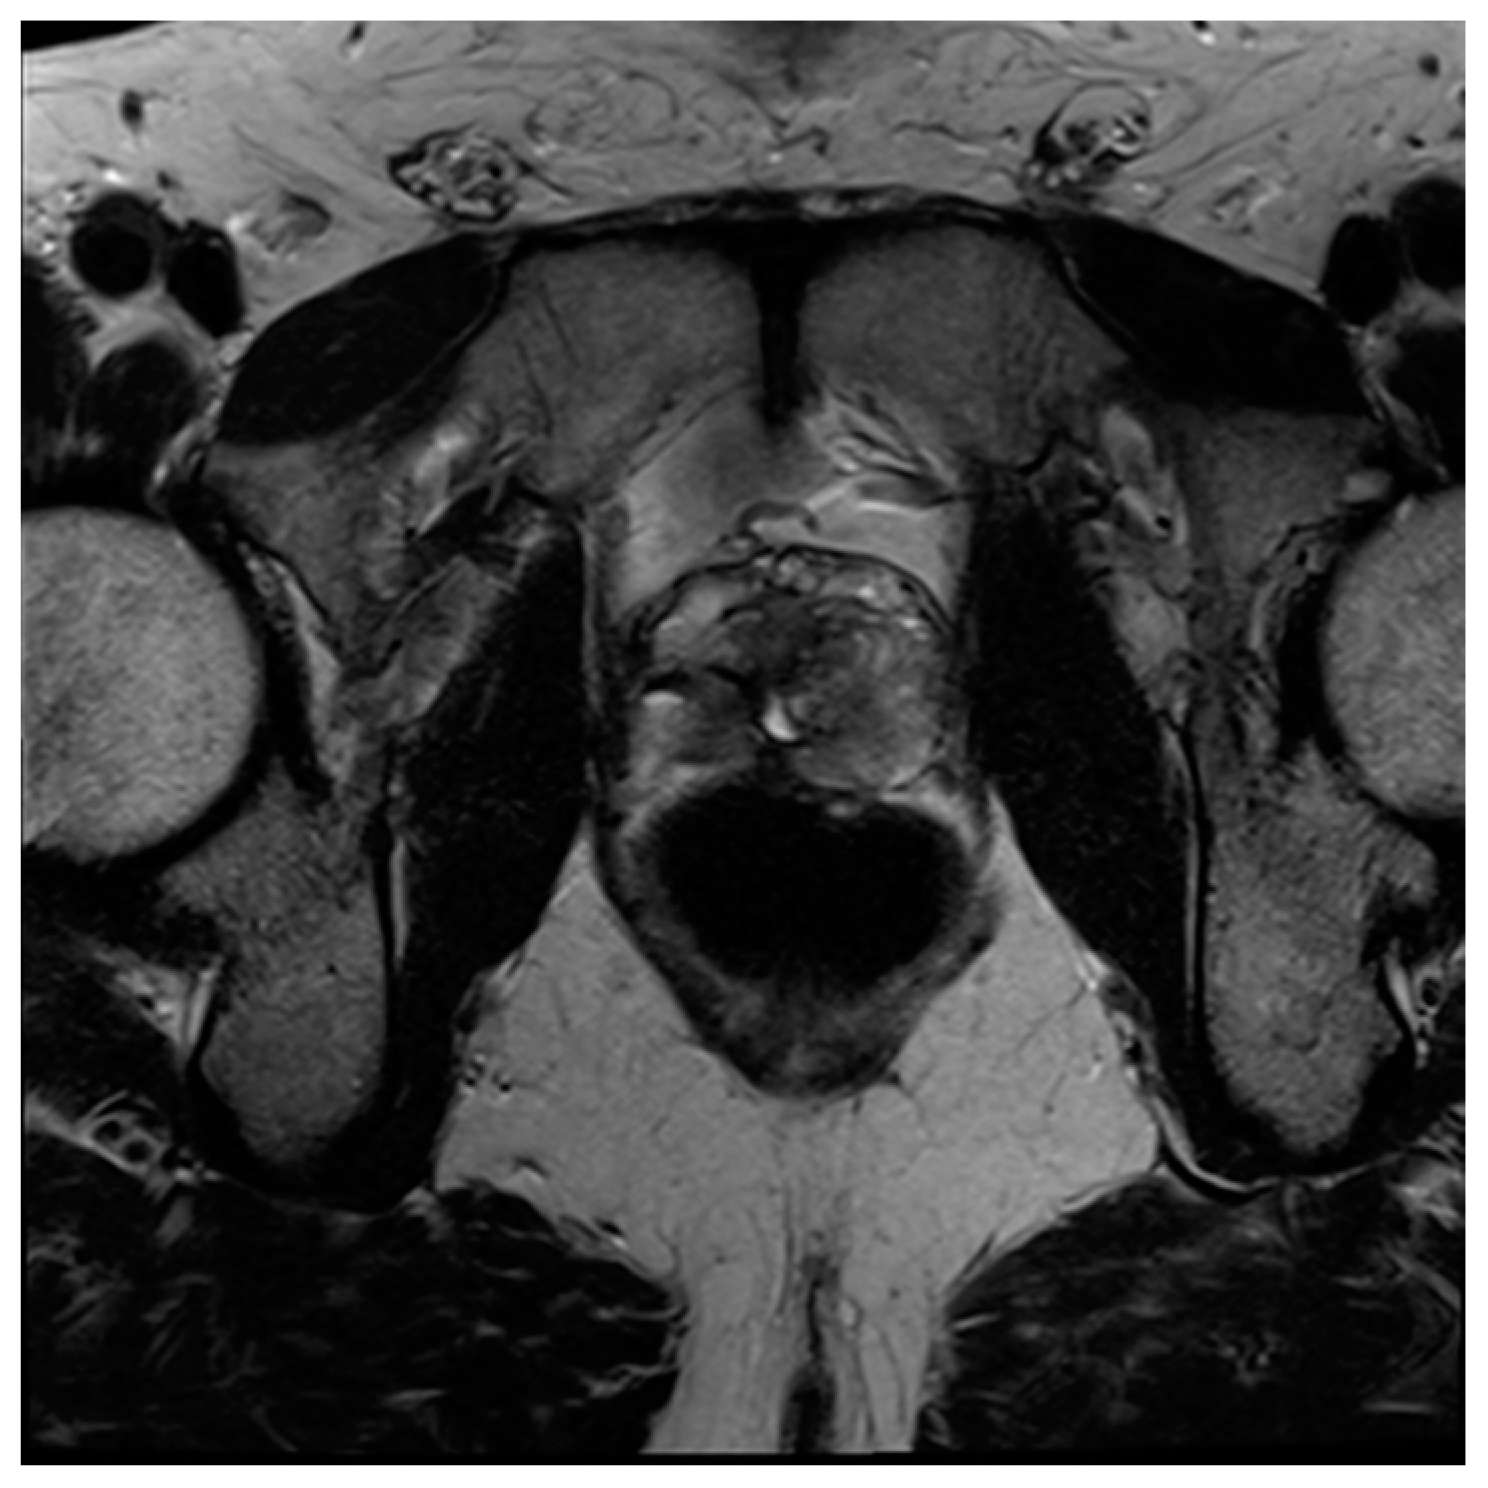

Figure 6. Sagittal T2 image demonstrating post-HoLEP changes to the prostate. As compared to TURP, HoLEP features a wider central defect with less residual peripheral tissue.

Laser enucleation of the prostate (LEP), commonly performed with either a holmium laser (HoLEP) or a thulium laser (ThuLEP), is an ever-increasingly used option for the treatment of BPH. These lasers were first used to vaporize tissue but are now more commonly used to enucleate the entirety of the gland, which is then mechanically morcellated within the bladder in order to facilitate expulsion. One major advantage of LEP, when compared to TURP, is that it is size-independent and can be implemented as a surgical option for glands of varying sizes [71]. When using MRI, LEP procedures look very similar to TURP but often have less residual peripheral tissue and a wider central periurethral defect (Figure 6). There can also be increased T2 intermediate signal and heterogeneity, which can impair the detection of prostate cancers.